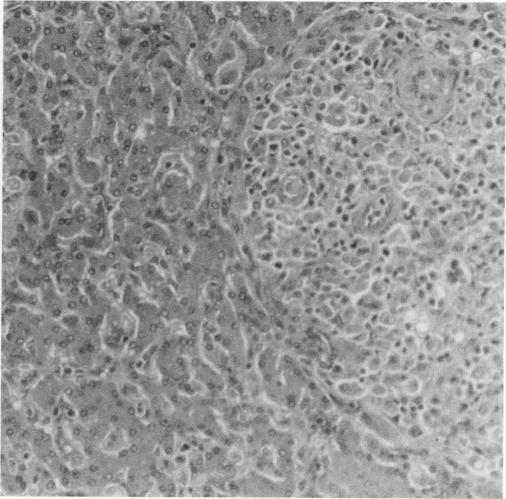

We describe the occurrence of acute monocytic leukemia in a dog with X-linked severe combined immunodeficiency (XSCID) that had been raised in a gnotobiotic environment for 20 months. This case represents the first reported instance of malignancy in canine XSCID, the first case of acute monocytic leukemia in any species with severe combined immunodeficiency, and the first documented malignancy in any species with XSCID that was not associated with immunotherapy.

我们描述了一只患有X连锁重症联合免疫缺陷(XSCID)的犬发生急性单核细胞白血病的情况,这只犬在无菌环境中饲养了20个月。该病例是犬XSCID中首次报道的恶性肿瘤实例,是任何重症联合免疫缺陷物种中的首例急性单核细胞白血病病例,也是任何XSCID物种中首例有记录的与免疫治疗无关的恶性肿瘤。